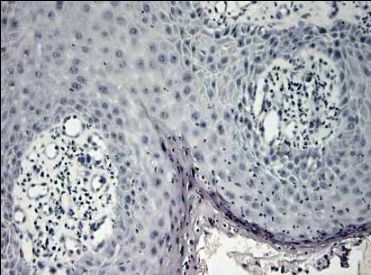

První bioptické vyšetření byla excize z třísla velikosti asi 6 mm s klinickou diagnózou karcinom vulvy v.s., provedená 7.7. 2006. Vzhledem k bohaté vaskularizaci epiteliálních čepů byl tento nádor patologem diagnostikován jako angiokeratom (Obr.2)

Obrázek 2